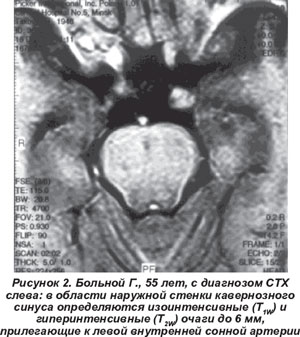

Аутоиммунный СТХ развивался не только после переохлаждения, перенесенных накануне инфекций, но также после стрессов. Чаще страдали мужчины (59,6 %). Характерными особенностями заболевания были: острое начало (76,9 %), неполные формы (83,1 %), умеренный или выраженный болевой синдром (80,7 %) и высокая эффективность терапии глюкокортикоидами (92 %). Среди заинтересованных черепных нервов чаще вовлекался глазодвигательный нерв. У 25 % больных при классических симптомах его поражения (птоз, расходящееся косоглазие, ограничение движений глазного яблока вверх и внутрь) наблюдался нормальный диаметр зрачка. При аутоиммунном СТХ были достаточно характерны: рецидивирующее течение - в 28 % и белково-клеточная диссоциация в СМЖ (0,44-1,87 г/л) - в 44 % случаев. Экзофтальм легкой или умеренной степени (20-24 мм) встречался только у 19,2 %, а хемоз - у 10 % больных. Проведение вызванных зрительных потенциалов у 4 чел. из 14 пациентов выявило субклиническое поражение зрительных нервов. Рутинные исследования крови не выявили патологии. При исследовании иммунного статуса в сыворотке крови наиболее существенным нарушением у половины больных была активация клеточного и/или гуморального иммунитета. Изменения содержания IgG в СМЖ были недостоверны. Отмечено значительное повышение интерлейкина-6 в сыворотке крови - до 0,13 ± 0,01 пг/мл (P < 0,05) и ФНО-альфа в СМЖ - до 0,109 ± 0,01 пг/мл (P < 0,05). Утолщение наружной стенки кавернозного синуса либо гранулемы при МРТ головного мозга обнаружены у 6 больных (рис. 2).

В последние годы в диагностике СТХ большую роль отводят методам нейровизуализации, так как проведение биопсии транссфеноидальным доступом обычно ограничено. T. Ozawa et al. [11] предложили МРТ-критерий СТХ: наличие в стенке кавернозного синуса патологической ткани, изоинтенсивной в Т1w-режиме и изогипоинтенсивной в Т2w-режиме. По данным La L. Mantia et al. [10], воспалительная инфильтрация или гранулемы в области кавернозного синуса при МРТ обнаружены в 44 (35 %) из 124 случаев СТХ. T.L. Haque et al. при МРТ выявляли маленькие очаги, примыкающие к краниальным нервам без распространения на кавернозный синус. При проведении МРТ в динамике после приема глюкокортикоидов авторы обнаруживали полное исчезновение очагов, что позволяет предположить их гранулематозный характер [4].